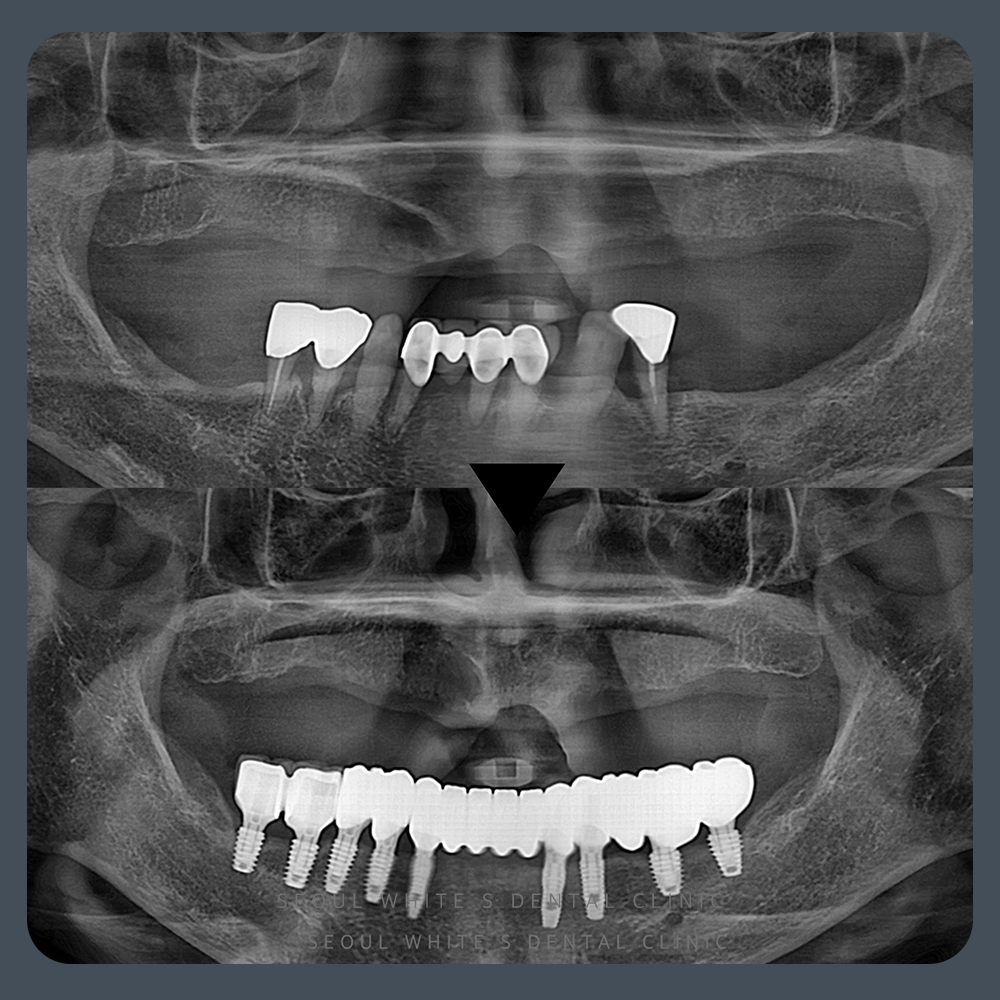

내원 당시 환자분은 윗니는 틀니를 사용 중이었고, 아랫니는 대부분 자연치였지만 전체적으로 심한 동요가 관찰되었습니다. 이 경우 치아를 억지로 살리는 것보다 예후가 나쁜 치아를 발치하고, 임플란트로 대체하는 것이 기능 회복에 훨씬 유리합니다.

정밀 진단 후, 잇몸뼈 상태를 확인한 결과 식립이 가능한 조건이었기에 디지털 가이드 수술을 계획했습니다.

치료 전에는 식사조차 어려워 하셨던 환자분은, 치료 후에는 건강한 모습으로 정기 검진을 받으러 오십니다. 아랫니 전체 기능이 복원되니, 발음, 저작력, 외모까지 동시에 좋아지는 변화를 경험하게 되었습니다!